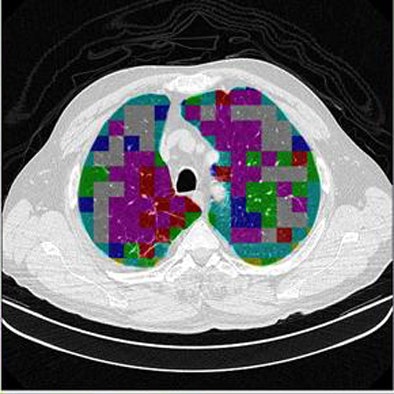

![]() |

| The classification algorithm training and test was performed using a 10-fold cross-validation methodology, which classified regions of interest in the lung parenchyma into nine patterns commonly seen on thoracic high-resolution CT images. The background and outside tissue classes indicate regions outside the lungs, while the remaining seven classes refer to patterns found in the lungs: normal parenchyma, ground-glass opacities, reticular and linear opacities, nodular opacities, honeycombing, emphysematous change, and consolidation. The classification step delivered an initial average accuracy of 61.6% (above). Eliminating the two most frequently confused categories, ground-glass opacities and consolidation, improved the average classification accuracy to 78%. |

| The completed CAD-analyzed cases are stored as a new series in the PACS server, where they can be examined side by side. In the color-coding system, normal parenchyma is white; ground-glass regions are blue; reticular-linear, green; micronodules, red; honeycombing, yellow; emphysematous changes, magenta; and consolidation, cyan. |